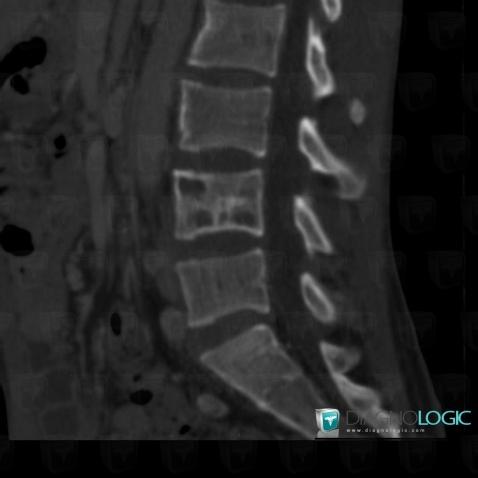

Tuberculosis, Vertebral body / Disk, Theoretical

Here is the specific information in the key image above:

- Diagnosis Tuberculosis (link to Osteomyelitis), Location(s) Vertebral body / Disk, with gamuts Vertebral fracture and vertebra plana